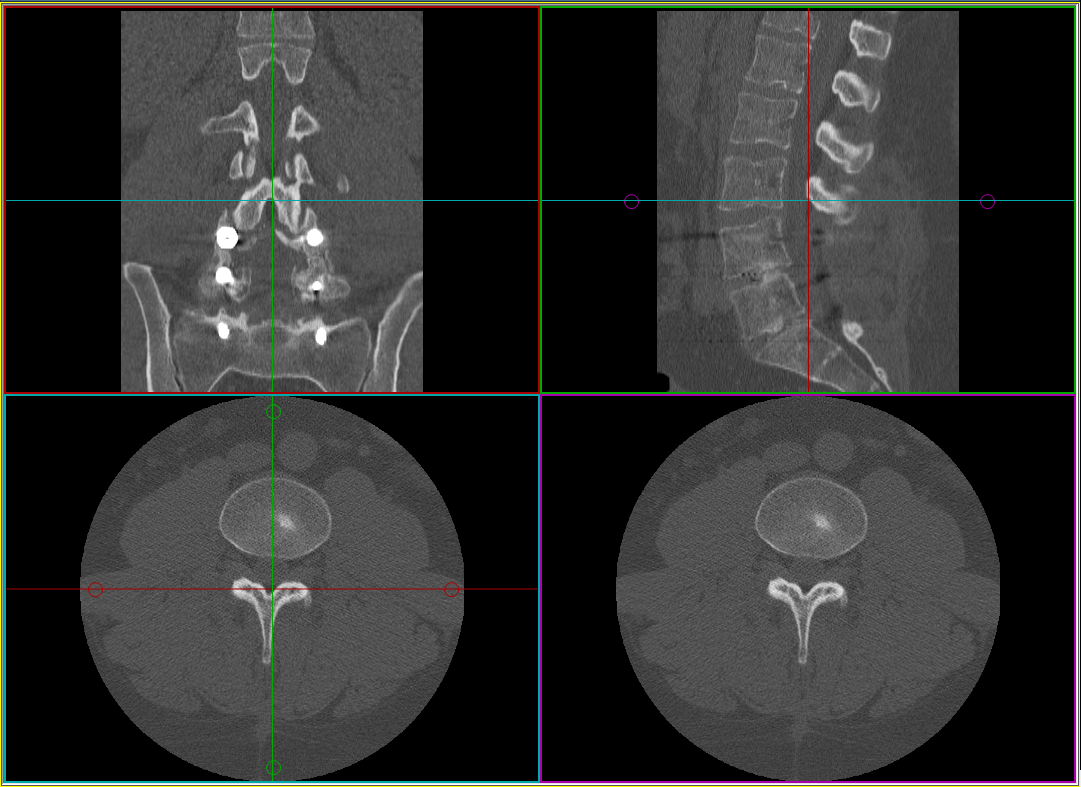

When the MPR frame is created, the image frame separates into four smaller frames. Each frame contains a single orthogonal view (sagittal, coronal, and axial) plus an oblique angle view. The oblique image frame is the results window, and is represented by the purple localizer in the coronal view. The other three frames are control windows. Color-coordinated localizers are available that match the color of the line to the color of the frame containing the image in that plane. Use these localizers to move and rotate the oblique image.